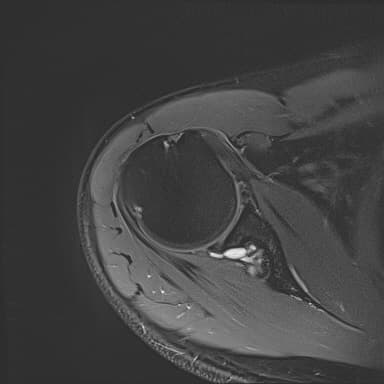

어깨 mri 좀 봐주세요 물혹있다고 하는데 수술해야 하나요?

하도 안 나아서 우측 견관절도 mri 촬영을 했는데 물혹이 있네요

팔에 힘이 안들어간다거나 방사통이나 아파서 잠을 깬다는점등은 현재 없는데...

이거 때문에 승모근이 잘 뭉치고 목이 뻣뻣한가요?

• 4번 째 사진